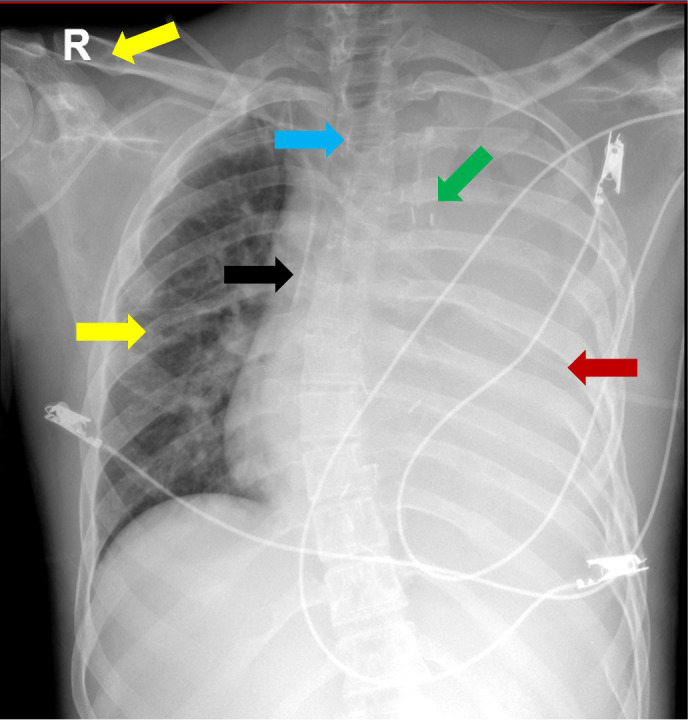

Case presentation: We present a case of a 19-year-old male with Gorham-Stout disease, multiple cervical lymphangiomas, and several thoracic complications successfully treated with sirolimus.

Abstract Image